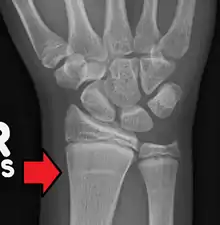

Harris lines

Harris lines are stress indicators on the skeleton that form due to malnutrition, disease, or other stress factors during childhood.[8] During this time, bone growth is temporarily stopped or slowed down but bone mineralization will continue. Once the stress has decreased or stopped, bone growth will resume, which results in a line of increased mineral density that can be seen in radiographs. If there is no recovery from stress, no line will be formed.[5][9]

Ameen et al. (2005) studied the incidence of Harris lines in medieval populations from Berne, Switzerland. the scholars from the University Hospital of Berne collected radiographs of the tibia from 112 well-preserved skeletons that lived during the 8th-15th centuries. They also compared their results with the radiographs of 138 living patients in the same geographic region. They found evidence of Harris lines in 88 of the 112 (80%) medieval skeletons and in 28 of 138 (20%) of the living individuals. In both populations, Harris lines were found at age 2 and between ages 8 and 12. The occurrence of Harris lines was associated with degenerative bone disease, trauma, osteoporosis, peripheral vascular diseases, rickets, rheumatoid arthritis, and bony deformities. The authors concluded that the medieval populations in Switzerland probably experienced difficult living situations and poor hygienic conditions and the Harris lines in children of the population reflected poor care and neglect.[10]